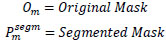

To evaluate the quality of the suggested model segmentation, we employed pixel-level metrics including accuracy, Dice coefficient, IoU, precision, recall, and F1 score. Table 3 represents the definitions of the metrics.

| S.No. | Metrics | Definition |

|---|---|---|

| 1. | Dice Score |

|

| 2. | Accuracy |

[32] [32]ee: True Positives, ff: True Negatives, nn: False Positives, mm: False Negatives |

| 3. | Precision |

|

| 4. | Recall |

|

| 5. | F1-Score |

[33] [33]

|

| 6. | IOU |

|